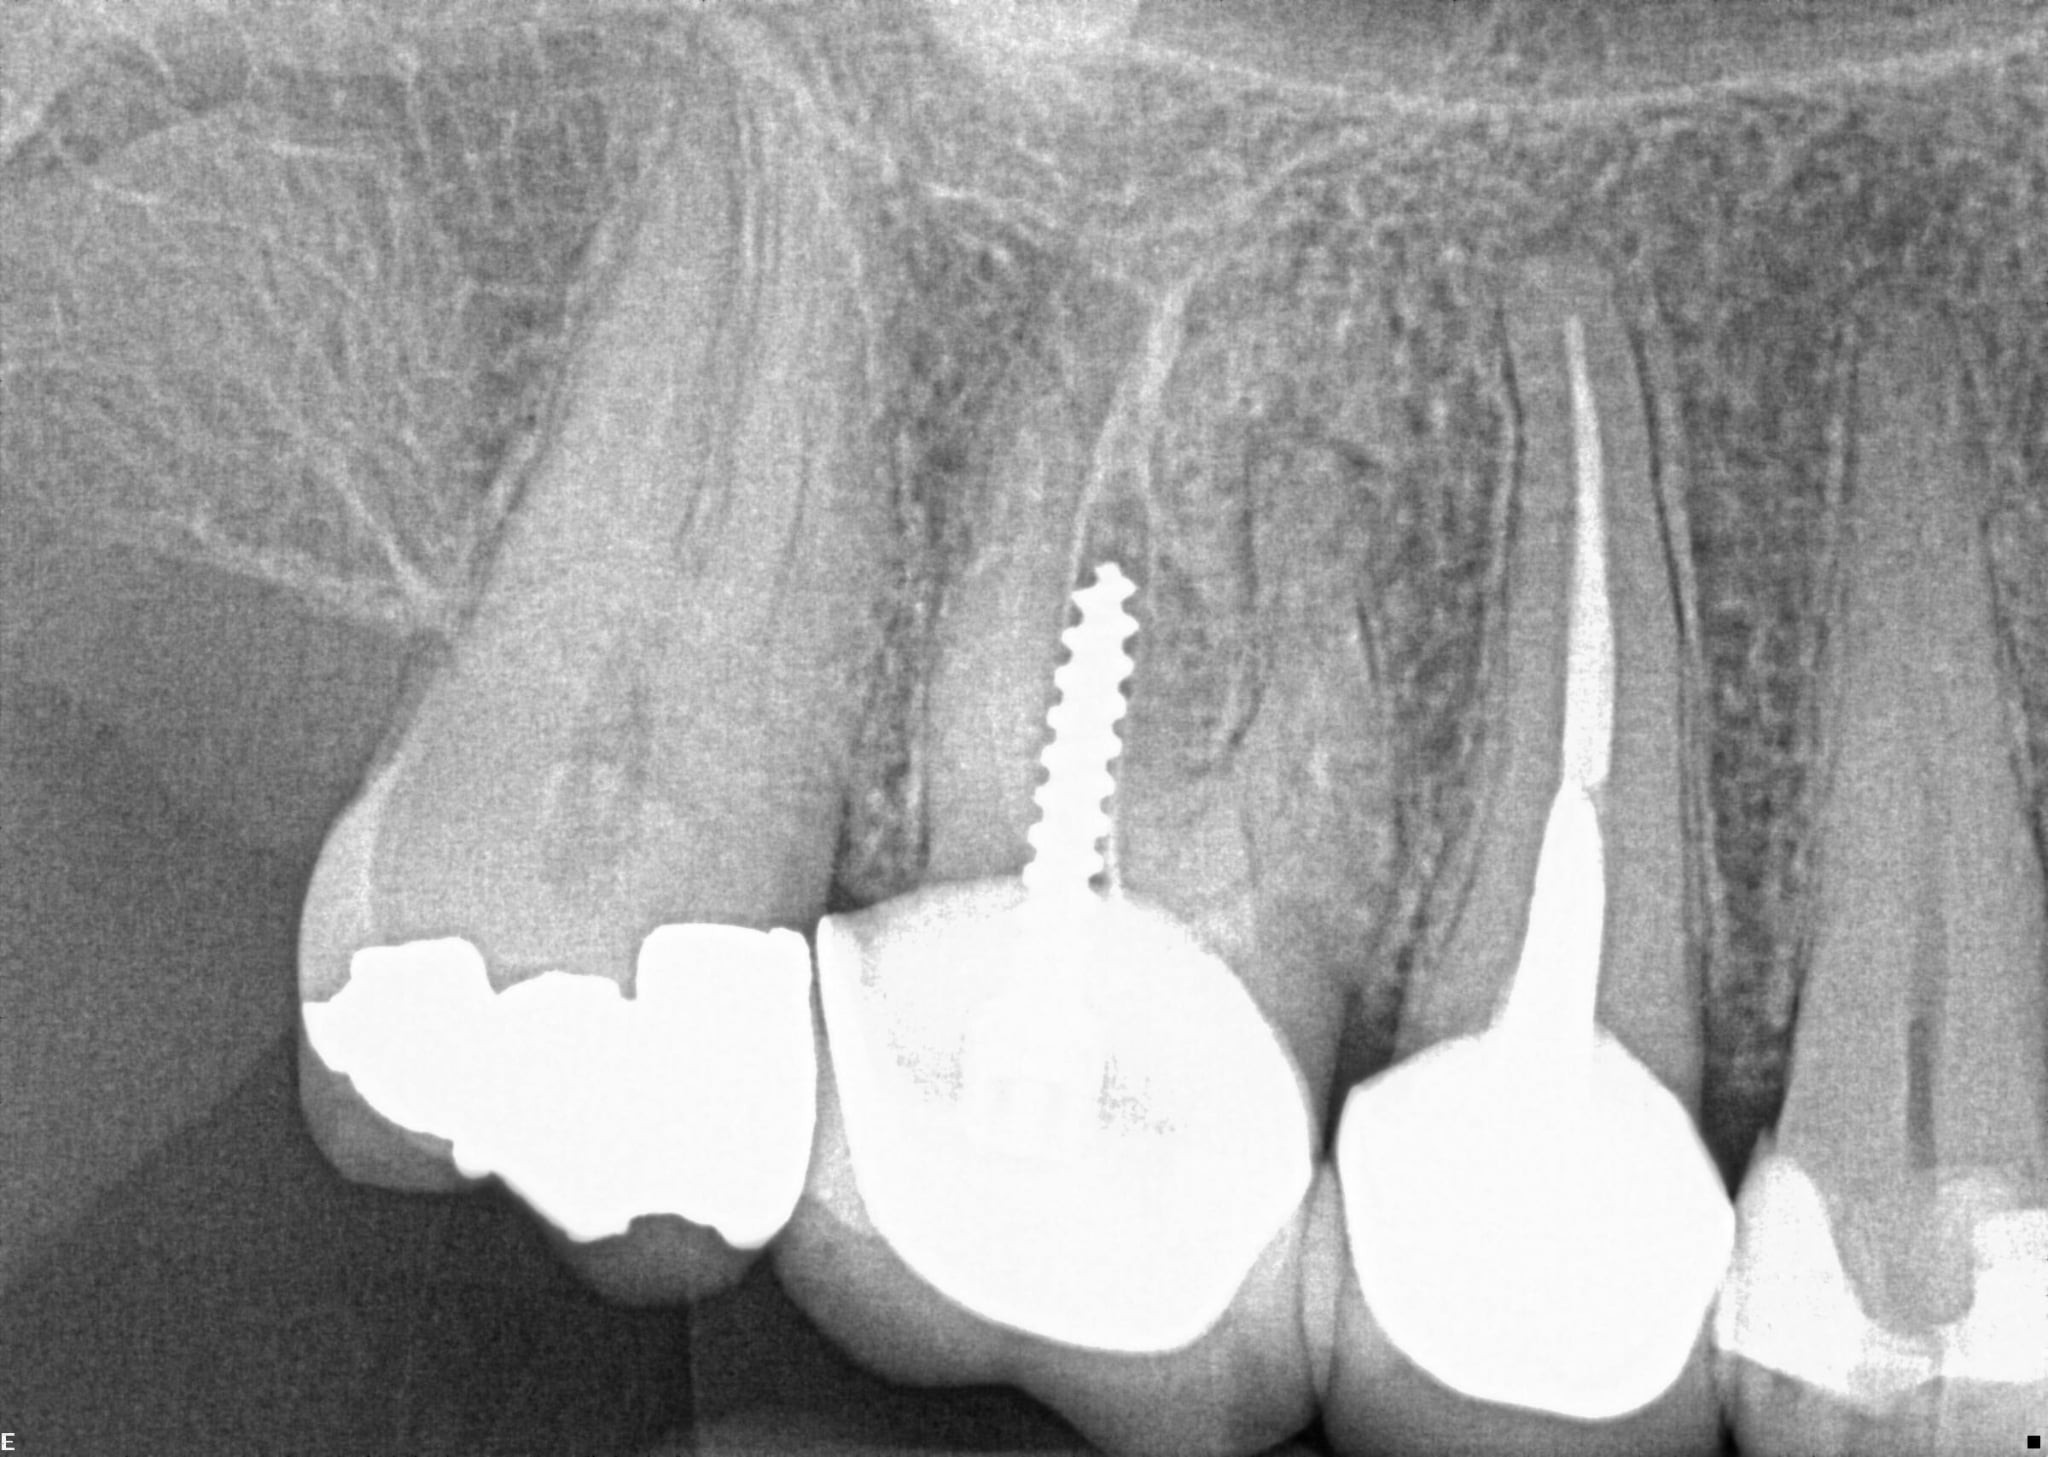

1. On which surface a recurrent caries can be detected?

2 / 35

2. On which surface a recurrent caries can be detected?

None of the teeth shows recurrent caries